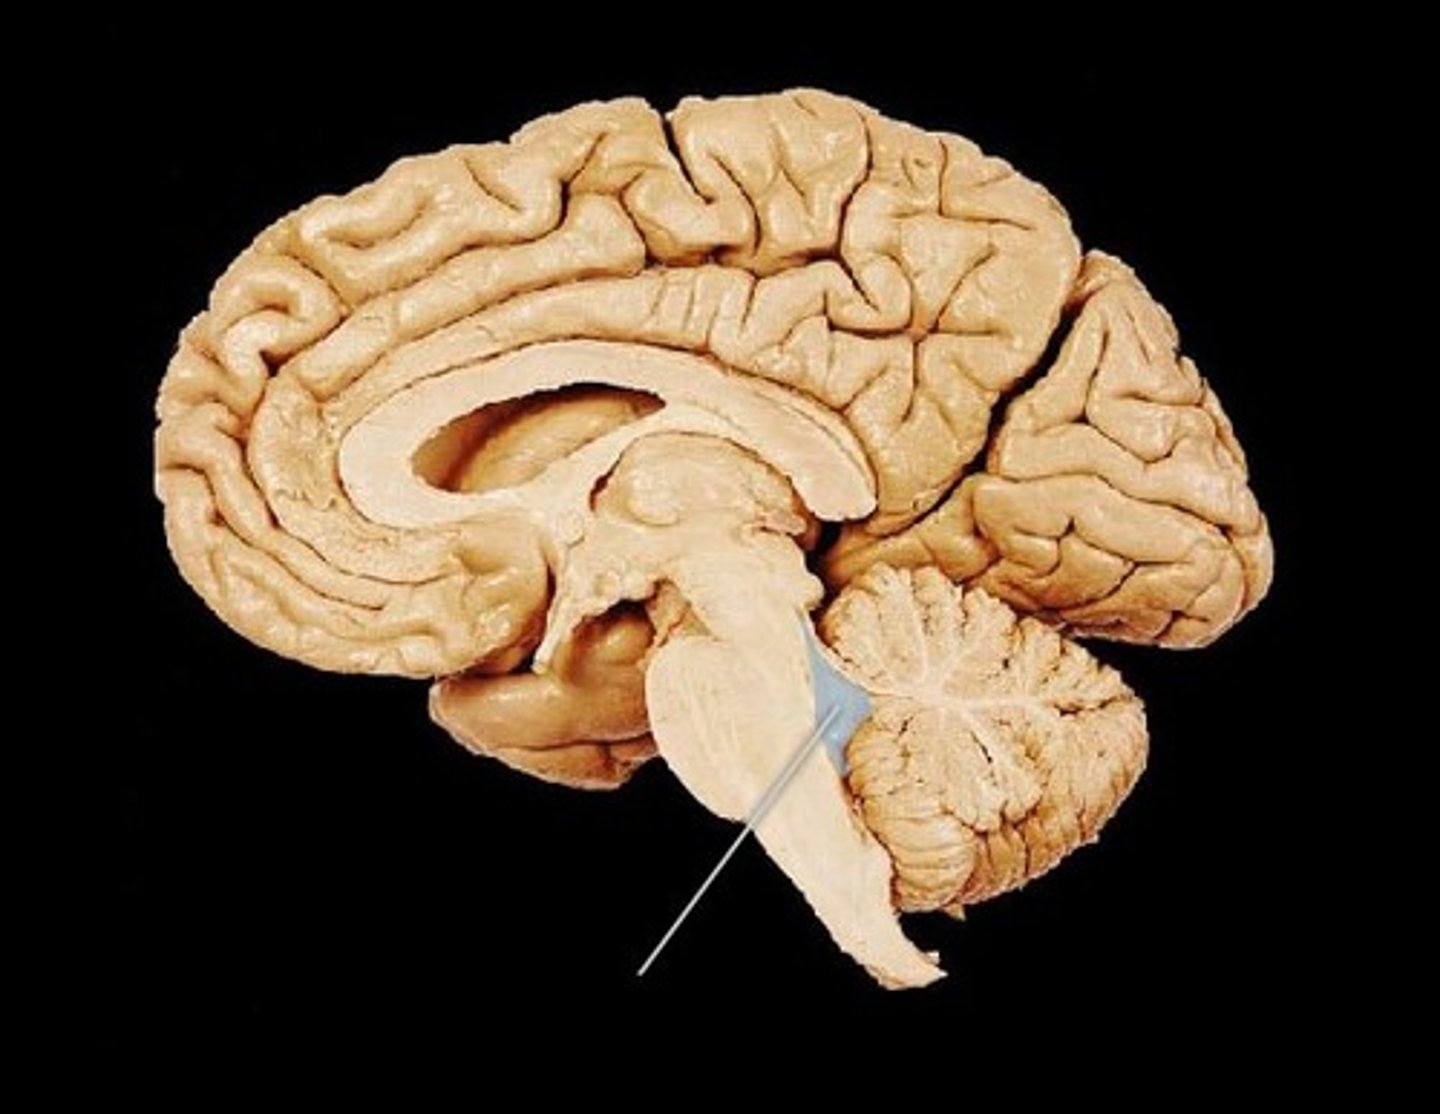

ventricles of the brain

canals in the brain that contain cerebrospinal fluid

fourth ventricle

between pons and cerebellum

cerebral aqueduct

connects the third and fourth ventricles

cerebral spinal fluid

made by choroid plexus

CSF function

buoyancy (supports 95% of the weight of the brain), protection (liquid cushion for brain tissue), chemical stability (transports nutrients to brain and waste away from brain)